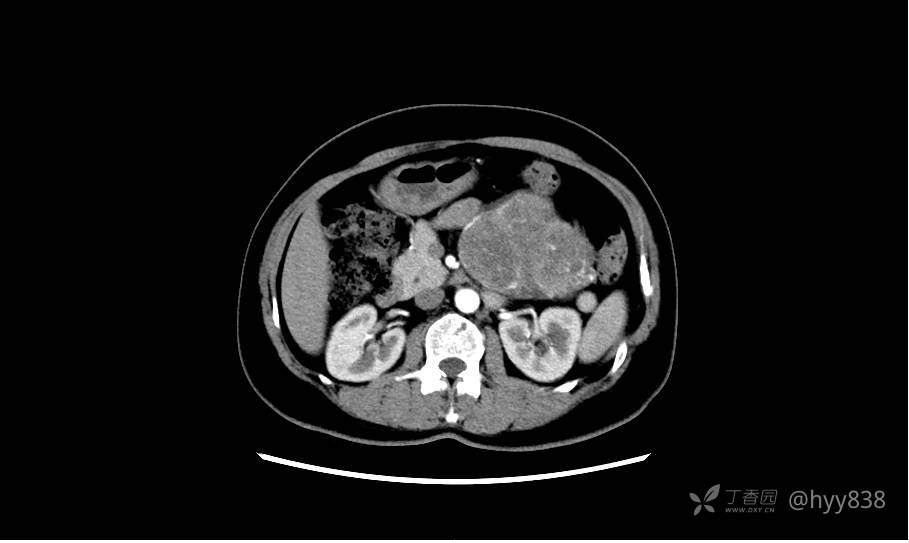

胰腺增强动脉期

静脉期(机器故障---延迟期了)